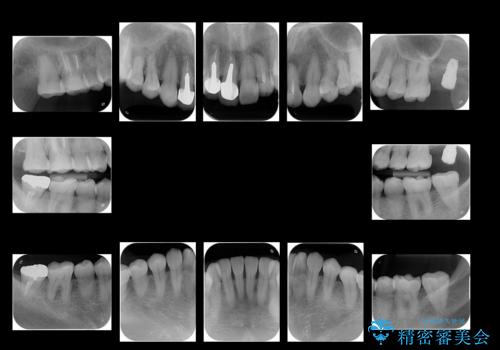

- 前歯のかぶせ物のやりかえと、全体的な治療をご希望して来院。

左上は他院でインプラントを入れたが、クラウンの脱離を繰り返して、仮歯に戻したあともうそれでいいと言われたとのことでした。

仮歯はすっかり劣化、変質しており、上記の写真のように隣の歯が虫歯になっている状態でした。

インプラントの製造会社は当院で使っているものと異なったため、ドライバー等購入し対応しました。

全体的にプラスチックで治療してあり、劣化していたのと、また、右上6番は根の治療がされていましたがプラスチックで埋めてあるだけで中を見たところ残念ながら割れていました。その歯は抜歯し⑤6⑦ブリッジにしています。